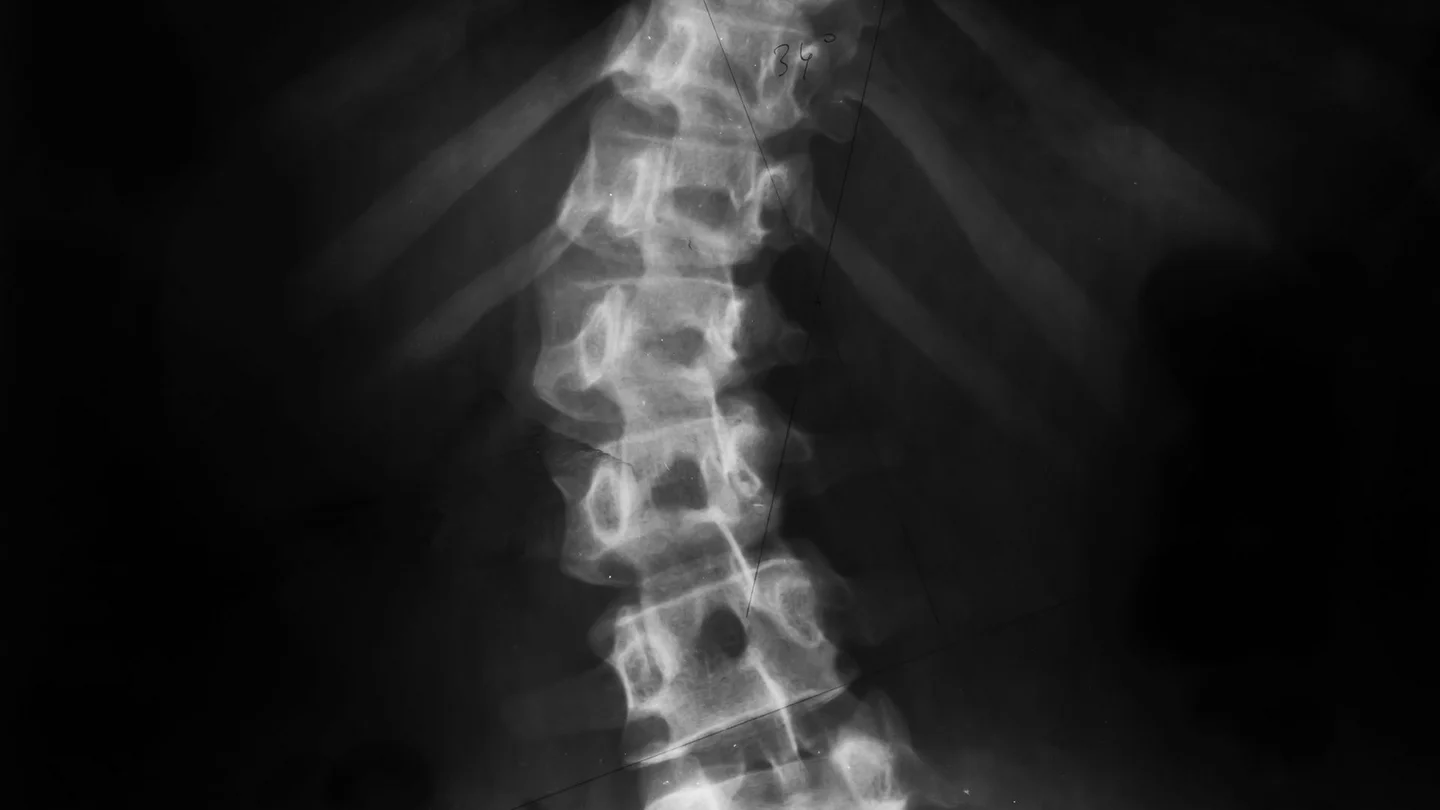

Skolyozda omurga farklı derecelerde eğri olabilir. Eğrilik derecesi Cobb açısı olarak bilinir ve bir röntgen filmiyle belirlenir.

- Ayakta dururken omurganın röntgen görüntüsü: Görüntü, eğriliğin ne kadar güçlü olduğunu gösterir ve Cobb açısını belirlemek için kullanılır.